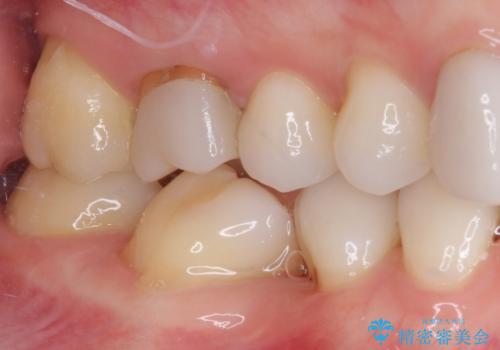

- 上下前歯のデコボコと奥歯の欠損を気にして来院された患者様です。

右下の欠損分は奥歯が倒れ込んでスペースがなくなっていたため、矯正治療により本来の位置に歯を移動させ、オールセラミックブリッジによる欠損補綴治療を行うこととしました。

全顎的にセラミッククラウンが多く装着されているため、インビザラインによる矯正治療を行うこととしました。

右下は移動量が多いため、十分な移動が達成されない場合はワイヤー装置を使用する予定としておりましたが、しっかりとマウスピースを装着してくださったため、前歯とともに十分に歯を動かすことができました。